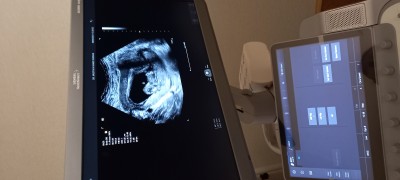

10+4 hamileyim Doktorum bebegin çıkıntılı var erkek olabilir ama daha küçük kordonda olabilir dedi benim içime de erkek doğuyor diğer 2 oğlumda da erken haftalarda öğrendim CANIM TUZLU ACI ISTIYOR TATLIYI KENDIMI ZORLAYARAK YIYORUM MIDE BULANTIM YOK BEL AGRIM COK :)

Gebelik haftası 10+4

Nub içinde 10 hafta erken yanılma payı yüksek oluyor 12 hafta cinsiyet tahmini için ideal bir hafta

Bebeğin cinsiyeti daha döllenme zamanında belli oluyor, ama kromozomsal olarak :) XX veya XY şeklinde. Doktorlar da sadece uzuvlara bakarak bilebilir @Minik Mucizee hanımefendinin dediği gibi aslında cinsel organlar da 12. haftadan itibaren az az seçilmeye başlanıyor. Yanılma payı yüksek 10. haftada, ama 2 hafta sonra daha net konuşulabilir. Bizimki önden poz verdi, sere serpe açtı bacak arasını net olarak gördük. Mini minicik testis yerleri bile netti :) Hayırlı olsun şimdiden :) Bir de yeme içmeyle ilgisi yok, ben çok kustum bulantım da oldu perişan etti beni, ama oğluşumuz olacak inşallah :)